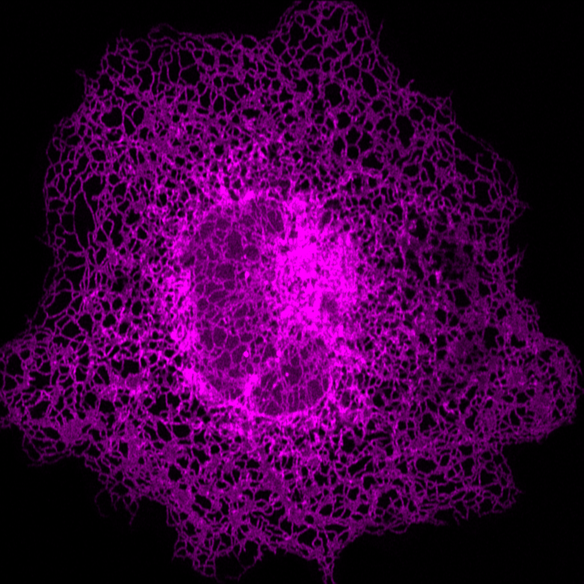

先进光学显微成像显示单个细胞内部的内质网

除此之外,研究人员还发现了一种新的内质网结构-片上管状内质网,更新了我们对内质网的认识,在科学上具有重要的创新意义。凭借在技术和科学认识上的显著创新性,该成果发表在全球顶级科学期刊《Nature Methods》(IF47.99)。